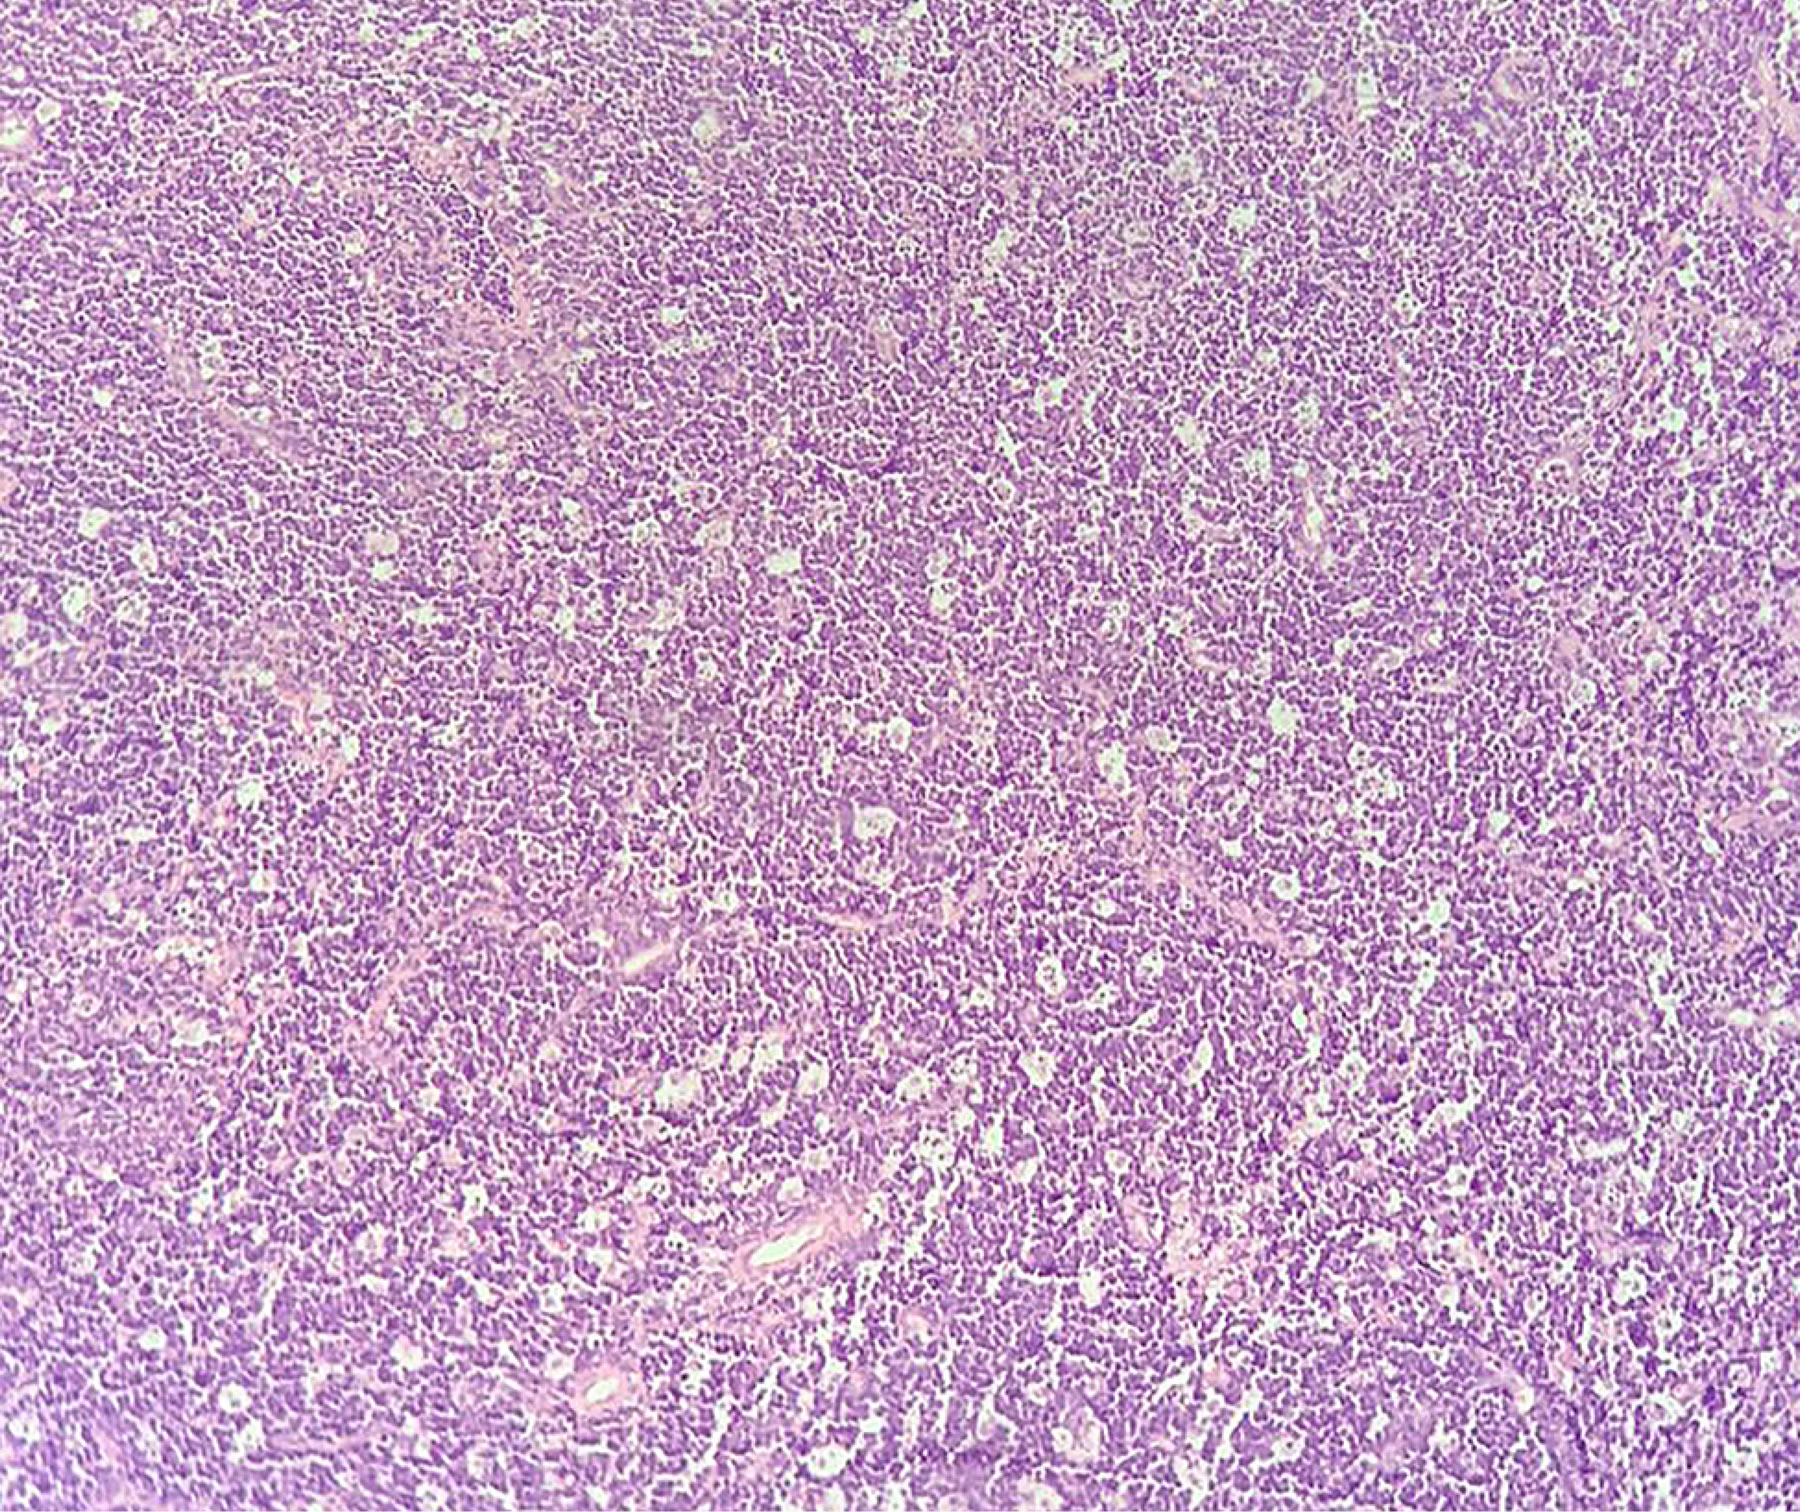

Se realiza biopsia ganglionar cervical derecho nivel II y biopsia transnasal de tumor primario. El informe histopatológico reporta linfoma no Hodgkin, de patrón difuso, células grandes de alto grado, probable linfoma de Burkitt (Figuras 2 y 3). Se realiza panel de inmunohistoquímica orientado resultando positivo para CD10 (Figura 4A), CD20 (Figura 4B), la Ki67 en 90% (Figura 5A) y C-Myc (Figura 6) y presentando negatividad para BCL-2 (Figura 5B) y CD3 (Figura 5C).

Para establecer el diagnóstico se requiere la combinación de parámetros genéticos, histológicos y por inmunofenotipo. Por histología se observan células homogéneas con núcleos ovales con nucléolos basófilos y citoplasma abundante y claro. Por la elevada actividad mitótica de estos tumores, los tejidos suelen mostrar el patrón de "cielo estrellado" por la presencia de macrófagos reactivos entre las células linfoides malignas, que contienen restos apoptóticos. Por inmunofenotipo es común que CD10, CD19, CD20, CD22 sean positivos. Además, es necesario que Bcl2 y CD3 sean negativos para descartar otros tipos de linfomas, así como demostrar translocaciones; la translocación t(8,14) (q2, q32) es la más frecuente. Sin embargo, la dificultad para la realización de pruebas moleculares hace que la histología e inmunohistoquímica sean suficientes para el diagnóstico.7-9

Figura 2

Figura 3